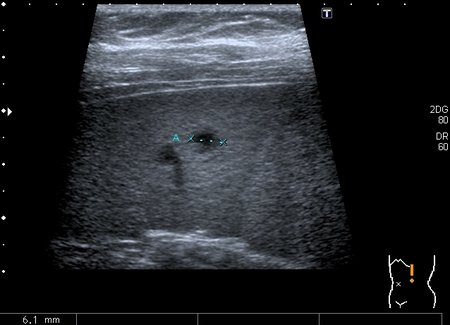

Девочка 13 лет, в течение 2-х недель температура до 38, СОЭ - 40 мм\ч, СРБ - 30.

На УЗИ: Учитывая клинику, лабораторные данные поставил гистиоцитарную инфильтрацию печени и селезёнки при генерализованной инфекции. Несколько раз встречался со схожими случаями, на фоне антибиотикотерапии изменения уходили. Но в данном случае девочка уже получала антибиотики в течение недели, на этом фоне не получено ни клинического , ни лабораторного улучшения, а на УЗИ очаги стали больше. Нужно ли расширять дифференциально -диагностический ряд? Ваши мнения

Имхо, по УЗ-семиотике - множественные небольшие абсцессы.

Мне нравится информация по данной патологии из видаровского "Клинического руководства по ультразвуковой диагностике в педатрии". Там данные изменения носят название очаговых поражений инфекционной этиологии (иерсиниоз, псевдотуберкулёз, токсокароз, хламидиоз и др.). Но инфекционисты, проведя ИФА с очень скудным набором диагностикумов и получив отрицательный результат, так же говорят, что это "не их".